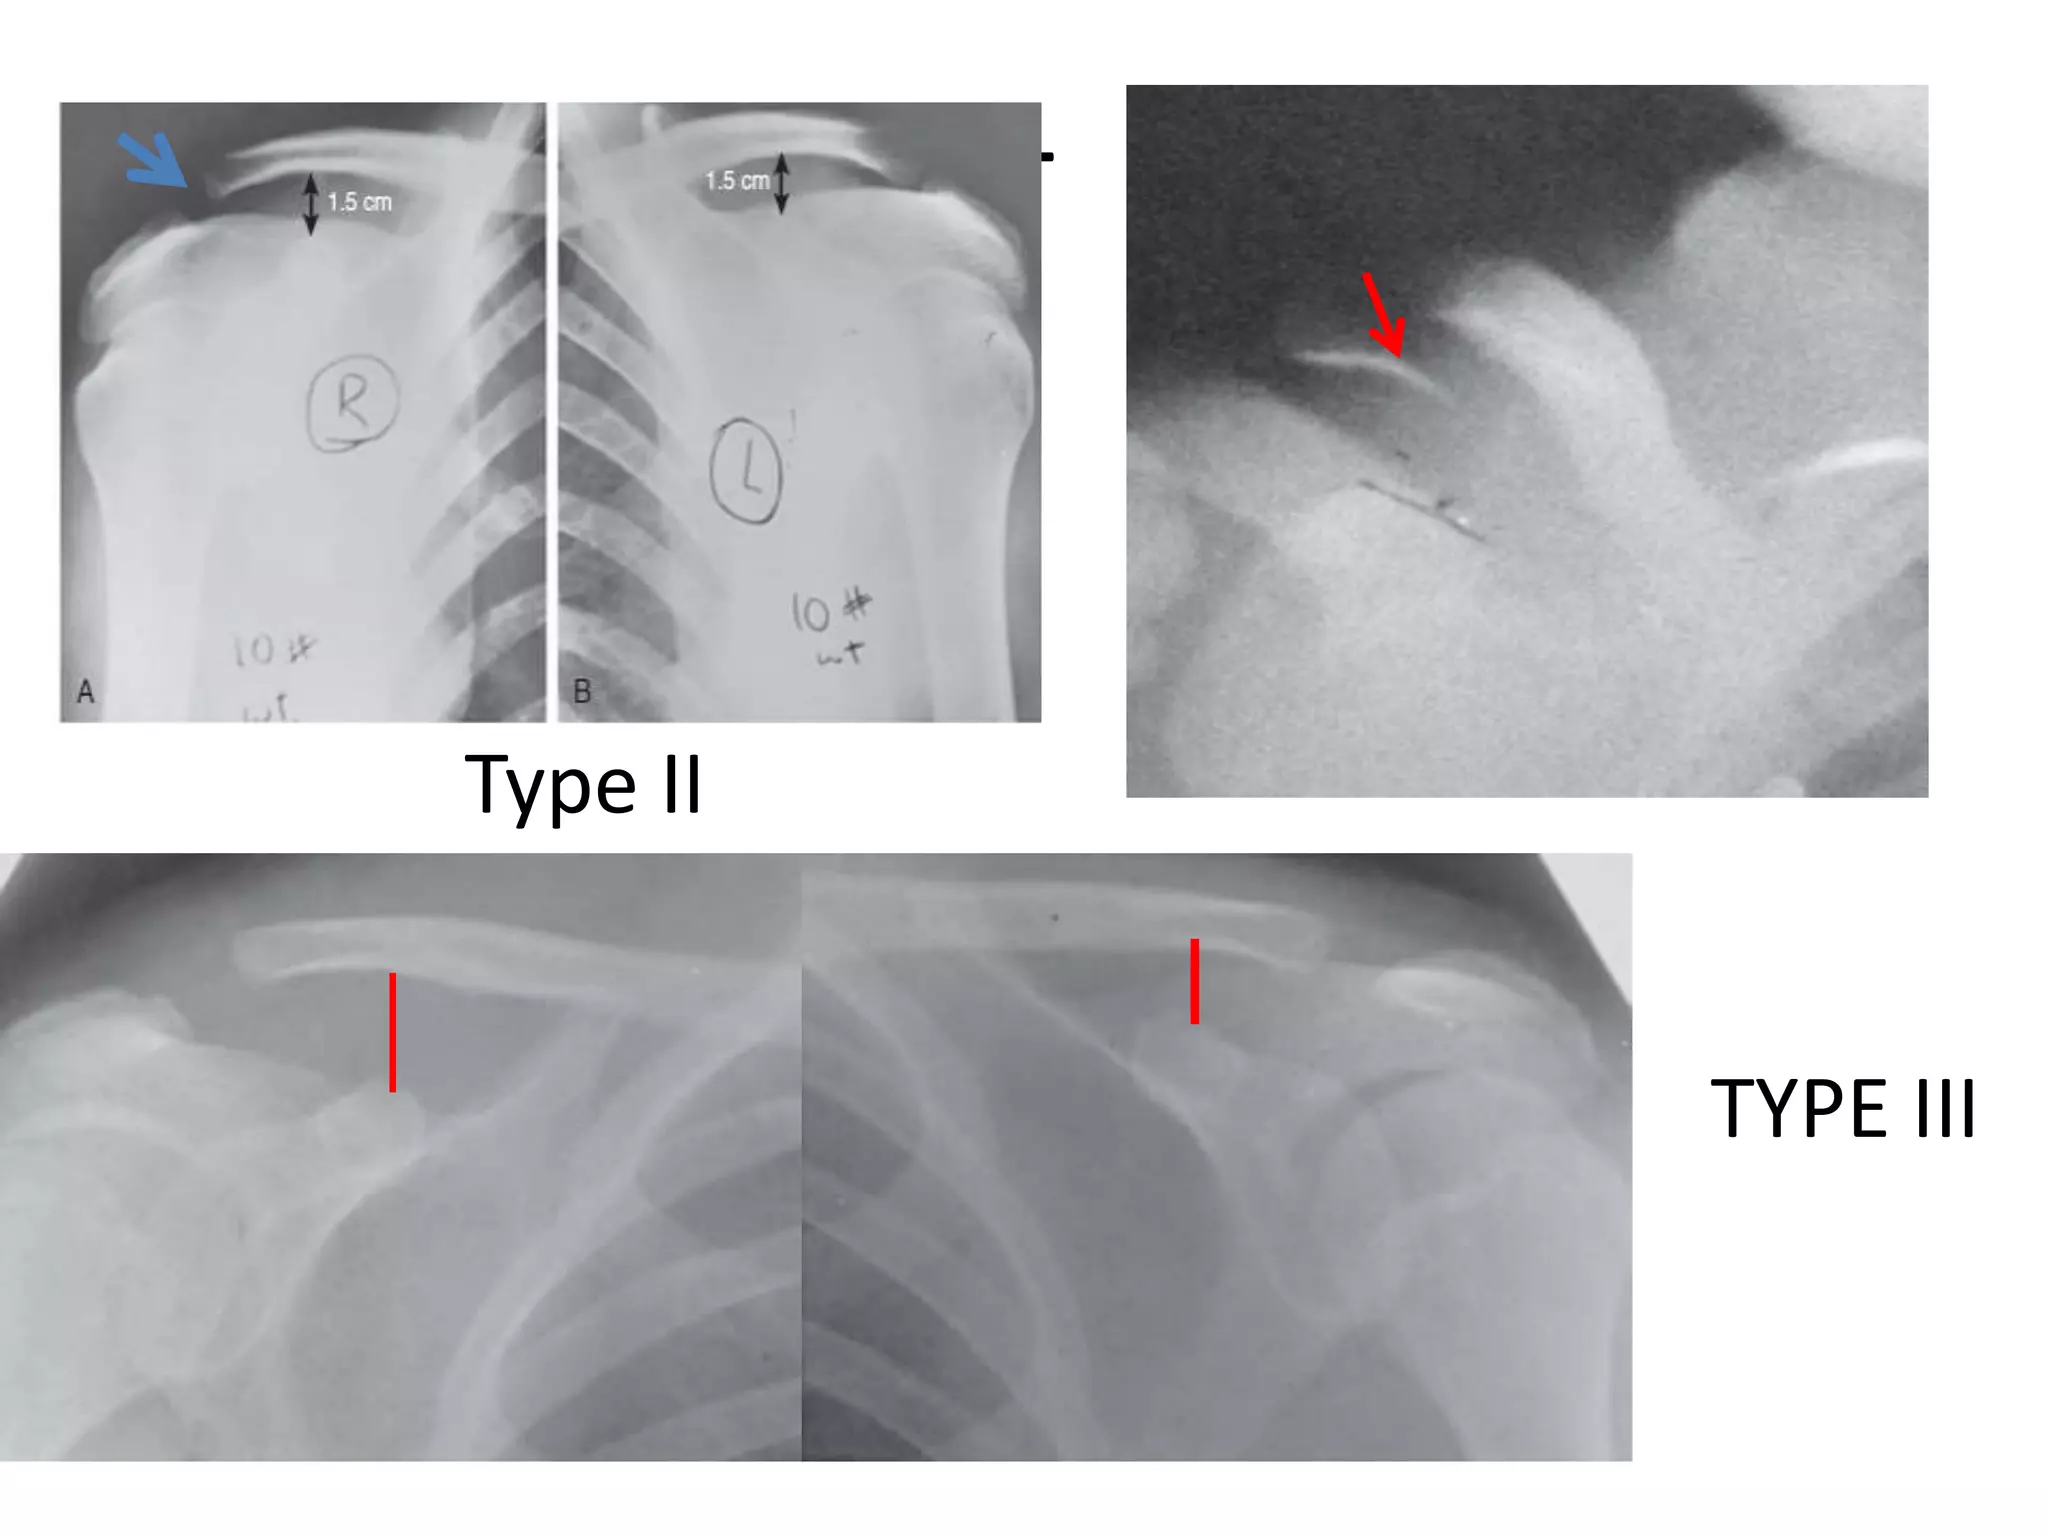

• Weighted-stress view of the AC joint : AP view

- maneuver to differenciate type II from III

5 kg

Type II

TYPE III